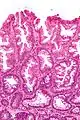

Histopathologie

La partie profonde des glandes est souvent élargie, a tendance à se diviser en deux ou trois branches et à s’horizontaliser, c'est-à-dire à se disposer parallèlement à la musculaire muqueuse et non pas perpendiculairement à elle, comme dans les polypes hyperplasiques conventionnels et les adénomes festonnés traditionnels.